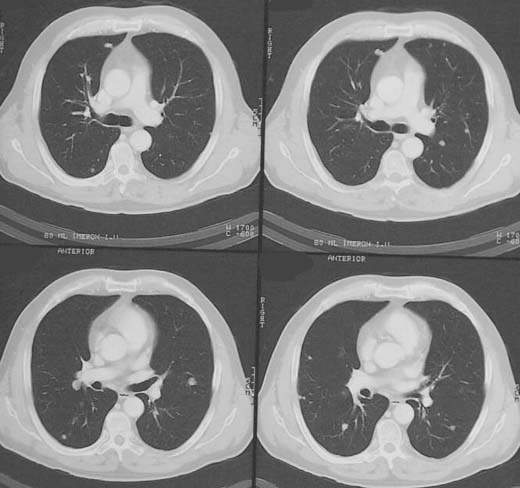

Patient, 53, Z. n. Rektumamputation bei Rektum-Karzinom.

Im

Lungenfenster multiple weichteildichte

Rundherde in mehreren Lungensegmenten.

Multiple Lungenmetastasen bei Rectum-Karzinom